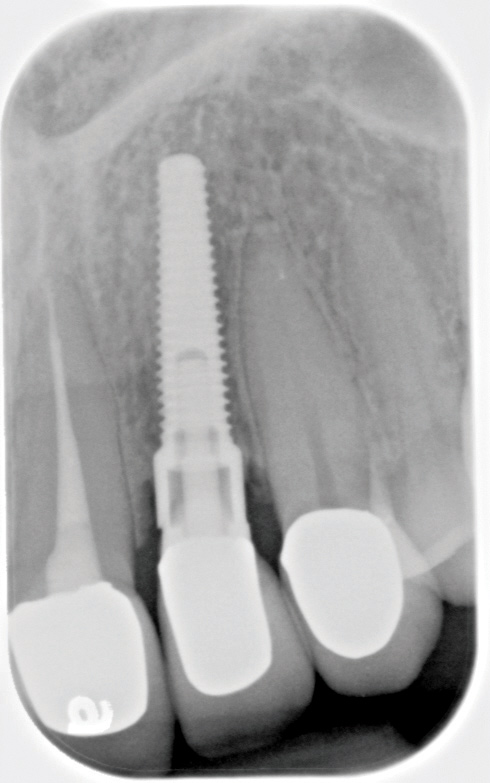

Fig 13. Radiograph depicting peri-implantitis.

Figure 13

Excess Cement Leading to Peri-implantitis

If all implant-supported crowns could be designed for screw retention, no discussion of excess cement would be necessary. However, screw retention is not always possible depending on the location of the access opening and because of the unesthetic appearance in anterior restorations or the mesial/distal angulation of the implant compromising the path of insertion (Figure 12). Residual cement left after crown cementation on implants can lead to peri-implant inflammation, peri-implantitis, and eventual loss of the implant (Figure 13 through Figure 15).25 The presence of lingering excess cement can encourage the development of bacterial colonization and peri-implantitis. Conversely, when too little cement is used, voids in the cement layer can occur and the prosthesis can become loose.26 The deeper the implant crown margin, the more difficult it is to remove excess cement.27

Radiopaque cements that contain zinc phosphate and zinc oxide (with and without eugenol) should be considered to help identify excess interproximal cement; however, this should be used secondarily to proper margin height and careful removal of cement during cementation. Resin cements lack the same opacity as zinc-containing cements and have been shown to be the most difficult to remove.28 Often in the process of removing this excess cement, the abutment surface becomes scratched and damaged, potentiating further plaque accumulation.29

Several modifications in abutment design and cementation have been suggested. Placing vent holes in the abutment during fabrication or leaving most of the screw-access chamber open for access has reduced the amount of cement that expresses out into the sulcus.26 It is also beneficial to extraorally express excess cement on an abutment replica prior to final crown seating to minimize complications. If retrievability is desired with cementable implant crowns, weaker cements (eg, zinc oxide eugenol) should be used first and progressively changed until the desired retention is achieved.